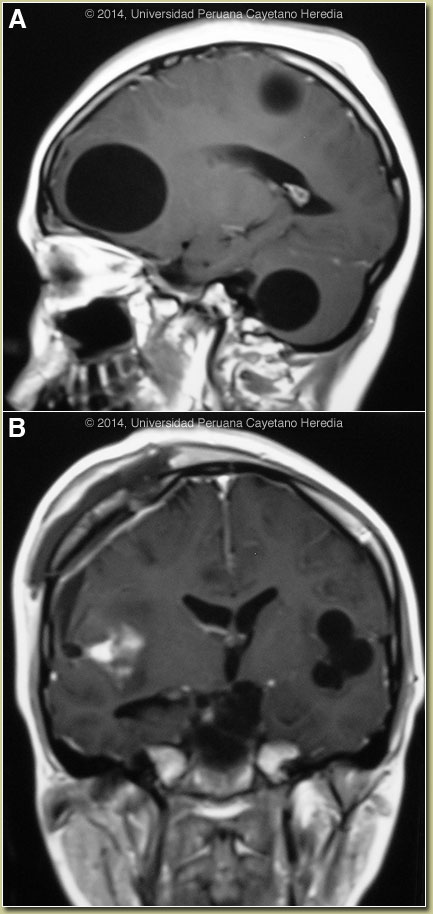

Discussion: A western blot was positive for E. granulosus. The radiologic appearance of cerebral hydatid cysts is almost pathognomonic as they appear in the parenchyma as large, unilocular spheres of homogenous CSF-density fluid with sharply defined thin borders and no surrounding edema. Images A & B show multiple parenchymal cerebral, brain stem and a right cerebellar cyst. Most cerebral hydatid cysts are supratentorial; they involve the middle cerebral artery, presumably due to the embolic nature of the infection. However, single large cysts are sometimes localized in the frontoparietotemporal subcortical region and brainstem lesions are quite rare [see